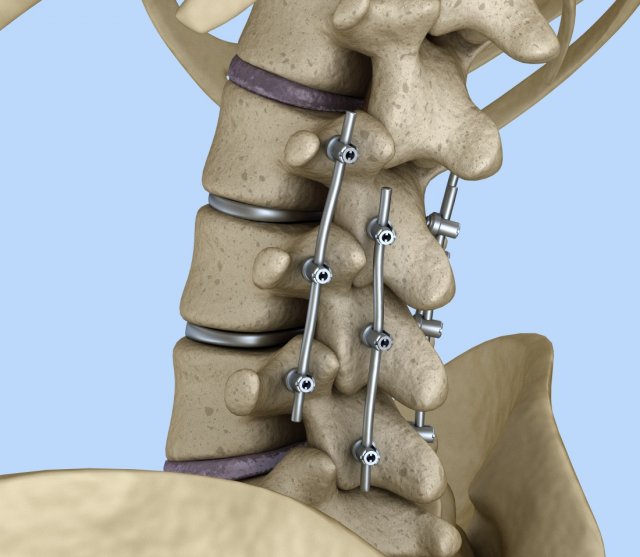

spinal fixation system - titanium bracket 3D 모델

spinal fixation system - titanium bracket. human spine, spinal cord, sacrum and fixation system medically accurate high quality 3d model.

hi-poly 3d model of human spine with internal structure.

please use hdri map (included) for reflections.

was used procedure materials for textures. if you want to use correctly colors and materials, please use max file.

you can control polygons by using meshsmooth function . 프린트 준비: 아니오

spine fixation spinal cord screw surgery system anatomy backbone bone brace bracer bracket column disc paralyze titanium treatment vertebra이 아이템에 대한 코멘트 없음.